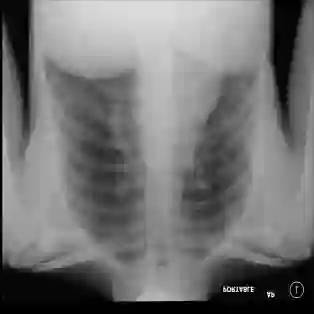

The COVID-19 disease was first discovered in Wuhan, China, and spread quickly worldwide. After the COVID-19 pandemic, many researchers have begun to identify a way to diagnose the COVID-19 using chest X-ray images. The early diagnosis of this disease can significantly impact the treatment process. In this article, we propose a new technique that is faster and more accurate than the other methods reported in the literature. The proposed method uses a combination of DenseNet169 and MobileNet Deep Neural Networks to extract the features of the patient's X-ray images. Using the univariate feature selection algorithm, we refined the features for the most important ones. Then we applied the selected features as input to the LightGBM (Light Gradient Boosting Machine) algorithm for classification. To assess the effectiveness of the proposed method, the ChestX-ray8 dataset, which includes 1125 X-ray images of the patient's chest, was used. The proposed method achieved 98.54% and 91.11% accuracies in the two-class (COVID-19, Healthy) and multi-class (COVID-19, Healthy, Pneumonia) classification problems, respectively. It is worth mentioning that we have used Gradient-weighted Class Activation Mapping (Grad-CAM) for further analysis.

翻译:COVID-19 疾病在中国武汉首次发现,并迅速蔓延到全世界。在COVID-19 流行病后,许多研究人员开始寻找一种方法,利用胸前X光图像诊断COVID-19 。早期诊断该疾病可以大大影响治疗过程。在本篇文章中,我们提出了一种比文献中报告的其他方法更快和更准确的新方法。拟议方法使用DenseNet169 和移动网络深神经网络的组合来提取病人X光图像的特征。在使用单向特征选择算法后,我们改进了最重要的特征。然后,我们将选定特征用作对光GBM(轻度推动机)算法的投入。为评估拟议方法的有效性,使用了ChestX-光8 数据集,其中包括病人胸部的1125 X光图像。拟议方法在两类(COVID-19,健康价值)和多级(COVID-19)中达到了98.54%和91.11%的缩略图。我们分别使用了“高度”的GRAMA-GRA级(C) 分别用于健康等级分析。